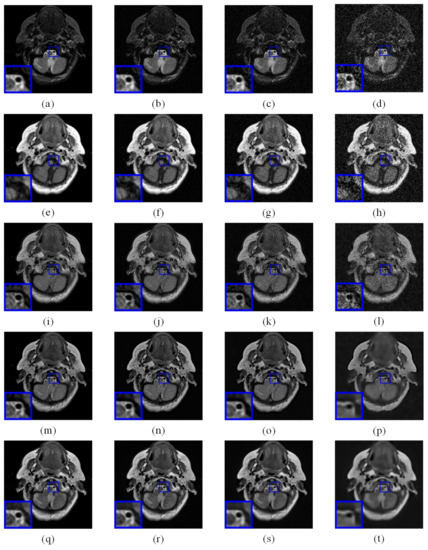

In comparative experiments, multi-focus, multi-modality medical and infrared-visible image pairs are employed. Noise is added to all source images for testing the processing performance. Noise levels of added noise are 0, 10, 20, and 50 respectively. The source images with noise level 0 are directly fused by conventional image fusion method in the comparative experiment. Representative fusion results are shown in Figure 10. Row 1 to 4 are the fused images with noise level from 0 to 50 respectively. The processing results of SDF is presented in image (a) to (l). Image (a)–(d), (e)–(h) and (i)–(l) are the processed results of multi-focus, multi-modality medical and infrared-visible image pairs respectively. (m)–(x) are the processed images by the proposed simultaneous image denoising and fusion method. Image (m) to (p), (q) to (t) and (u) to (x) are the processed results of multi-focus, multi-modality medical, and infrared-visible image pairs respectively.

According to the processed results shown in Figure 10, the proposed simultaneous image denoising and fusion method shows the best performance in brightness and contrast of the processed image. Parts of the processed images by SDF show the best performance in detailed information. However, since the denoising process affects the completeness of detailed information of source images, some detailed information of processed images is incomplete and unclear.

Figure 10. Comparison of separate and simultaneous image denoising and fusion results. (ad) and (mp) are denoising and fusion results of multi-focus image with additional noise σ = 0 , 10 , 20 , 50 by SDF and proposed method respectively. (eh) and (qt) are denoising and fusion results of malti-modality medical image with additional noise σ = 0 , 10 , 20 , 50 by SDF and proposed method respectively. (il) and (ux) are denoising and fusion results of infrared-visible image with additional noise σ = 0 , 10 , 20 , 50 by SDF and proposed method respectively.